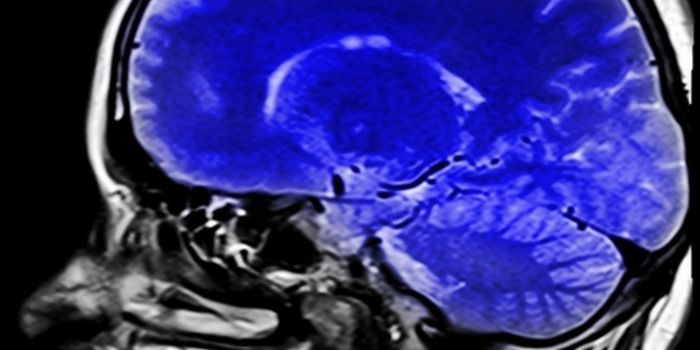

Read the latest articles about newly released neuroscience research and advances in experimental techniques. Topics include research news in neuroscience, neurology, psychology, brain science and cognitive sciences.